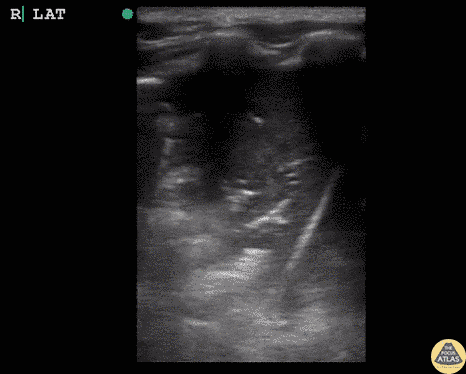

Question 1: A 50-year-old patient presents with dyspnea. fever, and cough. He started feeling poorly yesterday and has deteriorated steadily since then. His blood pressure is stable and he is requiring two liters of oxygen to maintain his saturation. This is the thoracic ultrasonography, starting at the diaphragm and moving upwards.

This is the ultrasound view with the probe held in place at the base of the lung.

- What radiographic finding does this correlate with on chest X-ray or CT scan?

- What are the most common causes of this type of radiologic pattern?

- What diagnosis do you think this patient has? Please try to be as specific as possible.

- What therapeutic regimen would you prescribe?